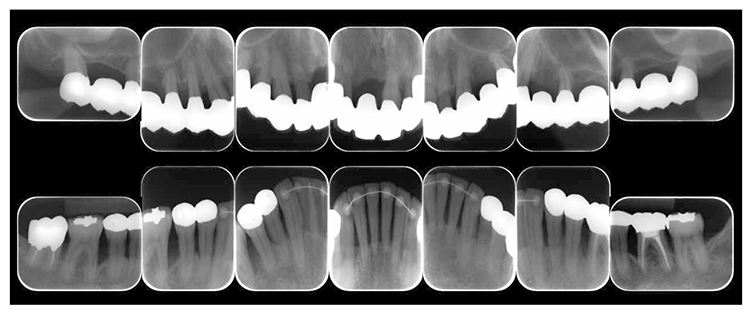

(3) X-ray findings

At the first visit, the findings showed moderate to advanced horizontal alveolar bone resorption in the entire jaw, and advanced vertical bone resorption on 24,36,46, 47. Additionally, on 46,47 were radiolucent findings that were likely associated with furcation involvement, and radiolucent areas on the alveolar bone surrounding the root apex were shown on 16,11,26. Furthermore, distally on 47, radiolucent findings showed caries extending into the dental pulp.(Fig.1c).

Fig 1c

(Fig.1c) Dental X-ray 14 during first visit (June 2007)